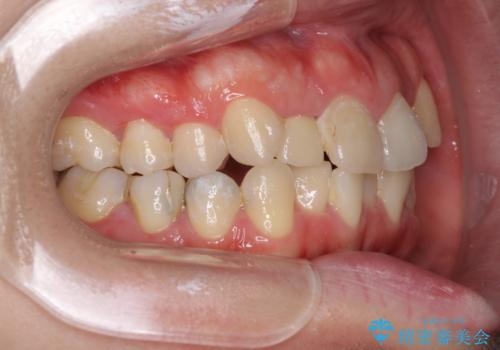

- 上下のデコボコと奥歯の咬みにくさを気にして来院された患者様です。

上顎骨の幅が下顎骨よりも小さいので、拡大装置により骨幅を広げて上下関係を改善し、その後インビザラインにて歯並びを整えることとしました。